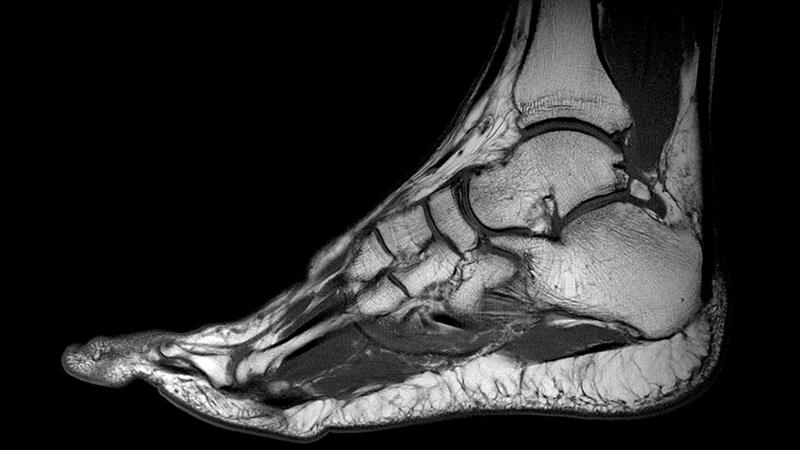

Кости голеностопа

Кости голеностопного сустава – малоберцовая и большеберцовая. К ним снизу присоединяется таранная. Под последней находится пяточная кость. Образовавшееся формирование выглядит как блок (это форма голеностопного сустава), в котором выделяют отдельные компоненты: наружную (внешнюю) и внутреннюю лодыжки и дистальную поверхность большеберцовой кости.

Голеностопный сустав располагается на месте стыковки берцовых костей (малой и большой) с пяточной костью, которая относится к стопе. Имеется 4 области голеностопа: задняя и передняя, наружная и внутренняя. Последние 2 располагаются в зоне лодыжек. Передняя – это тыл стопы, задняя – это зона ахиллова сухожилия.